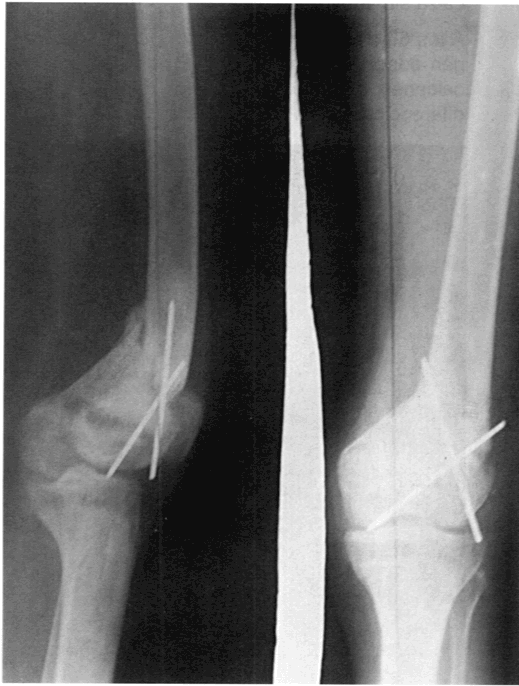

Control radiográfico de rodilla izquierda post-quirúrgico el 18 de octubre de 1991

Realiza rehabilitación kinesiológica sin fisioterapia.

A los seis meses se retiran los alambres de Kírschner pues hacían procidencia sobre la piel.